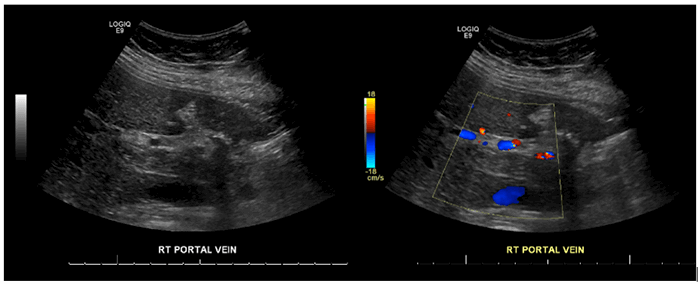

A 46-year-old morbidly obese African American woman presented with abdominal pain 13 days postlaparoscopic sleeve gastrectomy. Her pain was central and sharp in quality. She denied nausea, vomiting, or change in bowel habits. She also denied fever, chills, or dysuria. She was afebrile, hemodynamically stable, and her body mass index was 42.92. She had diffuse tenderness to deep palpation but did not exhibit peritoneal signs on exam. Labs were pertinent for mild leukocytosis, but electrolytes, blood urea nitrogen, and creatinine were within normal limits. Computed tomography (CT) of the abdomen and pelvis (Figure 1 and Figure 2) were suggestive of extensive portal vein thrombosis (PVT) that was confirmed with a follow-up ultrasound doppler study showing no flow in both branches as well as in the main portal vein (Figure 3 and Figure 4).

Figure 3. Echogenic intraluminal material in the right portal vein with no flow on color-flow doppler.

Figure 4. Color-flow doppler of main portal vein showing no flow.